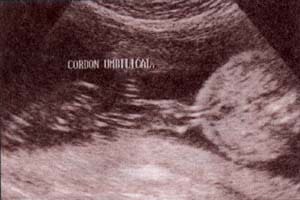

Diagnóstico Prenatal -  28 semanas. corte transversal Diagnóstico Prenatal -  30 semanas. corte transversal de cordón umbilical

fig. 52.– (c). 28 semanas. corte transversal que ilustra los tres vasos que componen el cordón umbilical, vena umbilical (1) y arterias umbilicales (2-3). fig. 52. – (d). 30 semanas. corte transversal de cordón umbilical de dos vasos. arteria umbilical (a) y vena umbilical (v).